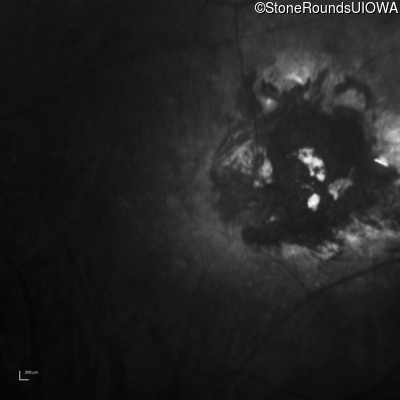

Infrared Fundus Photograph - Left - Count Fingers 2'

Exemplar